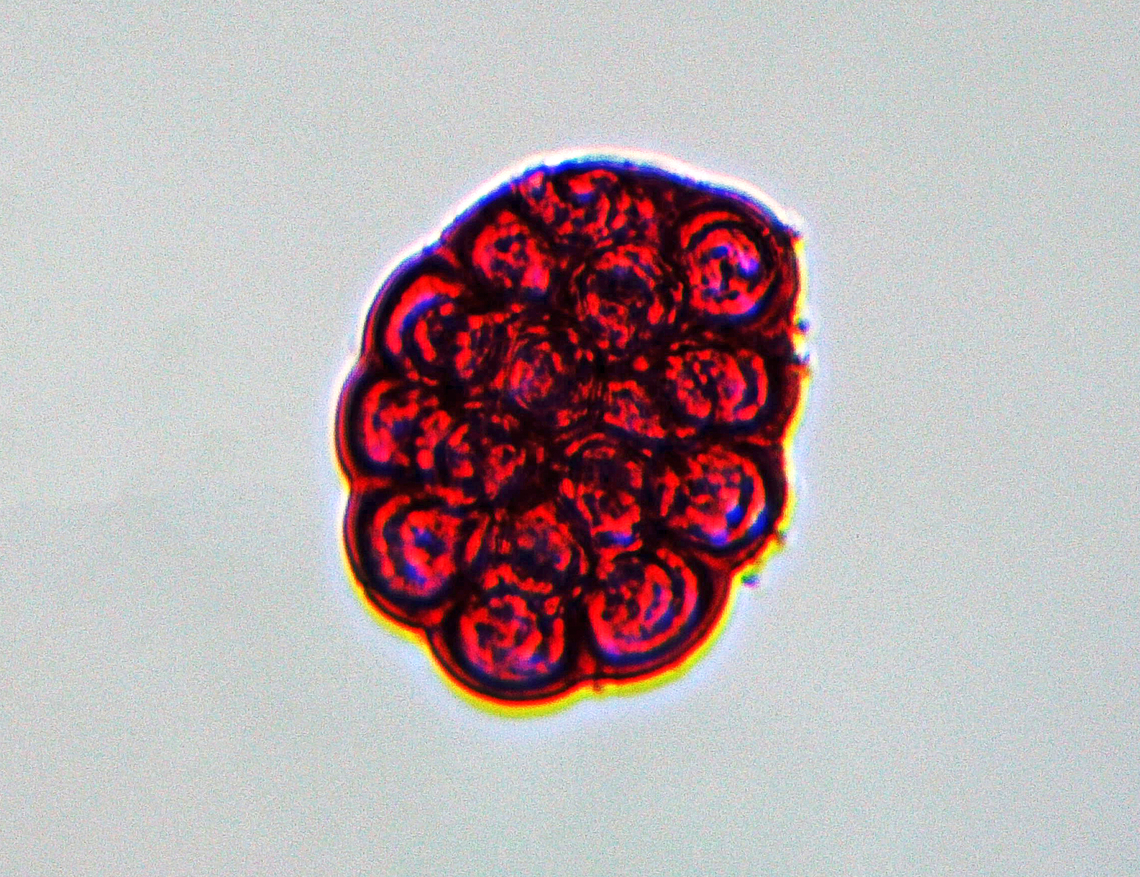

Flea Tapeworm Eggs - Dipylidium caninum

These are the eggs of the flea tapeworm.

This parasite infects organisms afflicted with fleas and lice, including dogs, cats, and human pet-owners, especially children. It occurs worldwide, and is the most common tapeworm of dogs and is also relatively common in cats.

"Dipylidium caninum," also called the flea tapeworm, double-pored tapeworm, or cucumber tapeworm, is a cyclophyllid cestode that infects organisms afflicted with fleas and canine chewing lice, including dogs, cats, and sometimes human pet-owners, especially children.